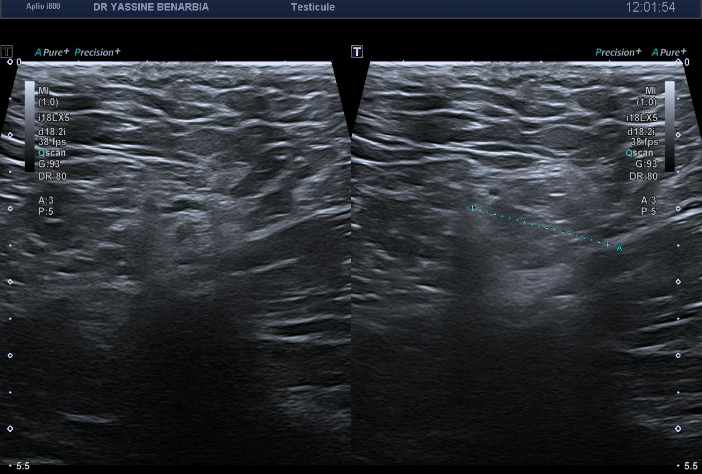

Une échographie testiculaire est donc réalisée. Diagnostic ?

L'échographie retrouve des testicules de morphologie, taille et vascularisation strictement normales bilatéralement. Les épididymes sont également normaux, sans signe d'inflammation. Le Doppler couleur montre une vascularisation testiculaire symétrique et physiologique.